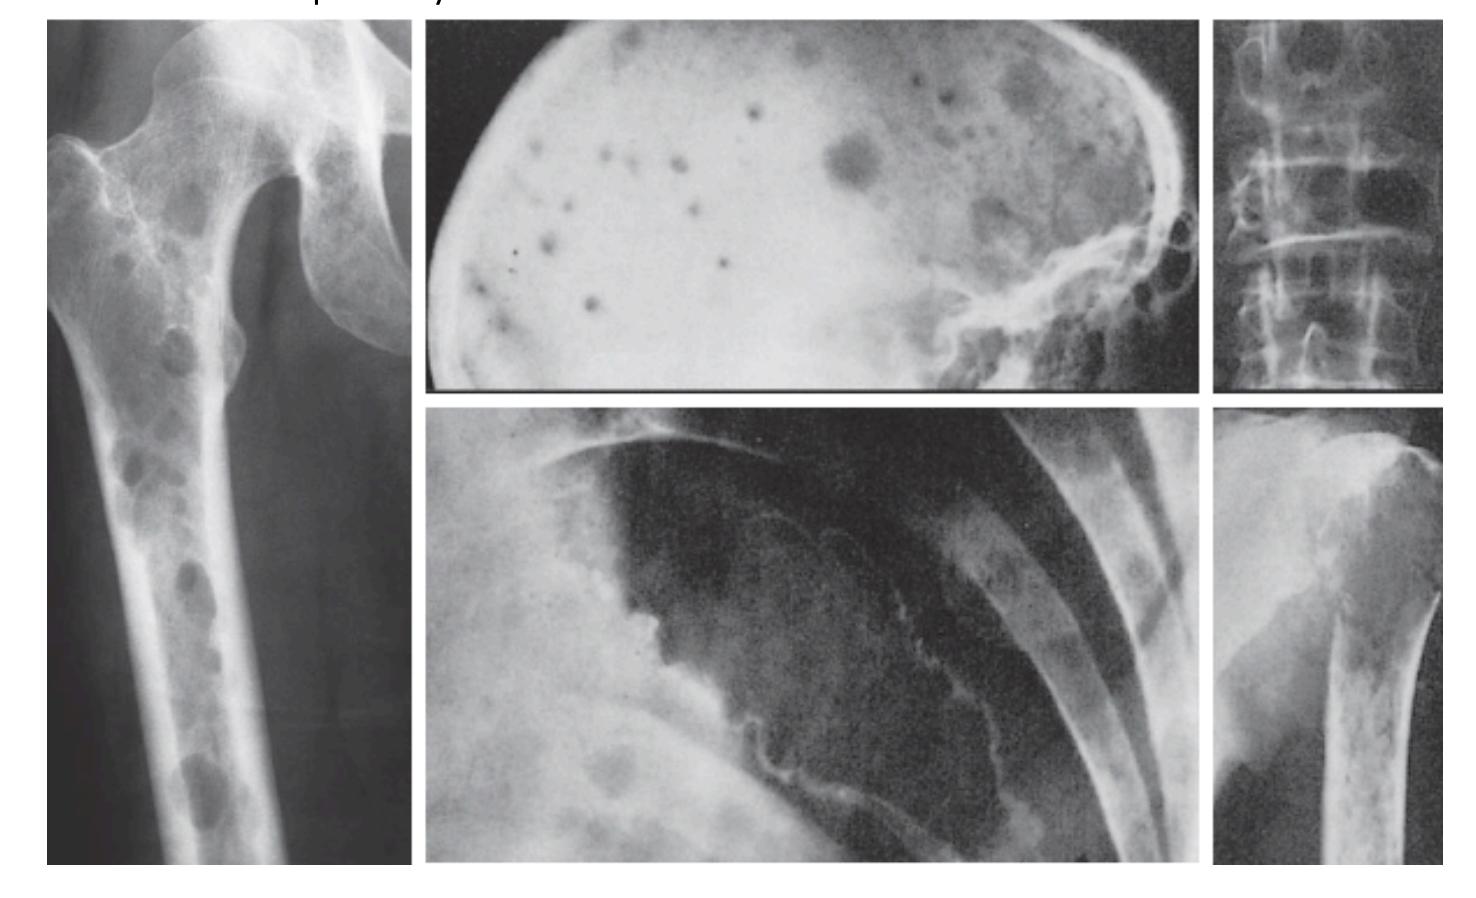

Osteosarcoma

Typical Presentation:

- Age: 10-20 years

- Pain and mass

- Location: Metaphysis of long bone

Characteristic Radiological Findings:

- Sunburst (Sunray) appearance

- Codmanโs triangle

- Periosteal reaction

- Bone eating appearance

Clinical Cases:

-

14-year-old patient with pain and swelling at lower right thigh

- Most important X-ray findings: Sun ray appearance, Codmanโs triangle

- Diagnosis: Osteosarcoma

14-year-old patient complaining of pain and swelling at lower R thigh

- Findings: Codmanโs triangle, Sun burst appearance

Ewing Sarcoma

Clinical Features:

- Occurs in children

- Throbbing pain

- Can be confused with chronic osteomyelitis

- Poor prognosis

11-year-old presented with symptoms - diagnosis on imaging

- Diagnosis: Ewing sarcoma

Case scenario provided with picture